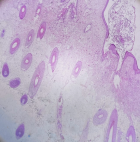

Therapeutic intervention: the severe symptomatology, the suspected complete adnexal torsion, and the young age of the patient led to the decision to perform an emergency laparotomy. The patient herself and her family were consulted about the necessity of emergency surgery. The laparoscopic approach was not available at our hospital. Intraoperatively, the presence of a large twisted ovarian mass, without signs of total necrosis, was found in the right parametrium. After immediate detorsion of the twisted adnexa and revascularization of the affected adnexa, a cystectomy with ovarian tissue preservation was performed (Figure 2). Histological examination of the surgical specimen (Figure 3) confirmed the diagnosis of a twisted ovarian dermoid cyst (Figure 4, Figure 5).

Figure 4: histological image of a twisted dermoid ovarian cyst: imaging of the cyst wall with hair follicles and skin is evident

Figure 5: histological image of a twisted dermoid ovarian cyst: imaging of nervous tissue with a choroidal plexus is evident